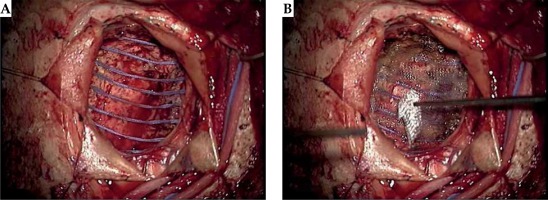

The patient, a 57-year-old male with a history of stage IV hypopharyngeal cancer, who was treated with chemotherapy and external beam radiation (70 Gy) to the neck in 2012. Two years later, the patient presented with a headache and was found to have a 1.5 cm left parietal lobe metastasis, which was treated with linac-based SRS to 20 Gy prescribed to an 80% isodose line on April 7th, 2015. Preoperative MRI on April 9th, 2015 revealed two metastases in the right frontal lobe and the right parietal lobe 1.9 cm × 2.3 cm × 2.4 cm and 2.7 cm × 2.2 cm × 2.9 cm, respectively (Figure 1). On April 10th, 2015, the patient had both the right frontal and right parietal lesions treated with one right frontoparietal craniotomy and with the immediate intraoperative placement of 131Cs brachytherapy. A gross total resection of both tumors was achieved, which combined to form one large cavity (over 5.3 cm total maximal preoperative tumor diameter). Minimal brain tissue was removed between the lesions, representing a total volume of approximately 0.5 cm × 0.3 cm × 0.4 cm. A total of twenty-six 131Cs stranded seeds with activity of 3.76 mCi were implanted, with a dose of 80 Gy to a depth of 5 mm from the perimeter of the cavity, using the technique described in our original published phase I/II trial [13]. We used preoperative magnetic resonance imaging (MRI) scans as well as our institutional physics nomogram to calculate the dose of the volume implant. This was adjusted intraoperatively for the change in intracavitary volume after resection of the tumor. The 10 cm, suture-stranded 131Cs seeds (0.5 cm inter-seed spacing) were delivered in strings of 10 seeds per string, subsequently cut into smaller lengths per the nomogram, and placed as a permanent volume implant along the cavity in a tangential pattern to maintain a 7 to 10 mm spacing between seeds. As a result, the combined cavity was lined with the seeds in a pattern like barrel staves or parallel tracks (Figure 2A). The 131Cs seeds were stranded and cut in real time in order to accommodate and precisely fit the resected cavity. The seeds were covered with surgicel (Ethicon) to prevent seed migration and alteration of dosimetry (Figure 2B), and tisseel (Baxter) was used to line the cavity to limit cavity shrinkage and further prevent seed dislodgement.

Fig. 2

A) Intraoperative photography demonstrating the resected cavity, intraoperative 131Cs placement, and sealing the procedure: the combined cavity was lined with the seeds in a pattern like barrel staves or parallel tracks. B) Intraoperative photography demonstrating the resected cavity, intraoperative 131Cs placement, and sealing the procedure: the seeds were then covered with surgicel (Ethicon) to prevent seed migration and alteration of dosimetry